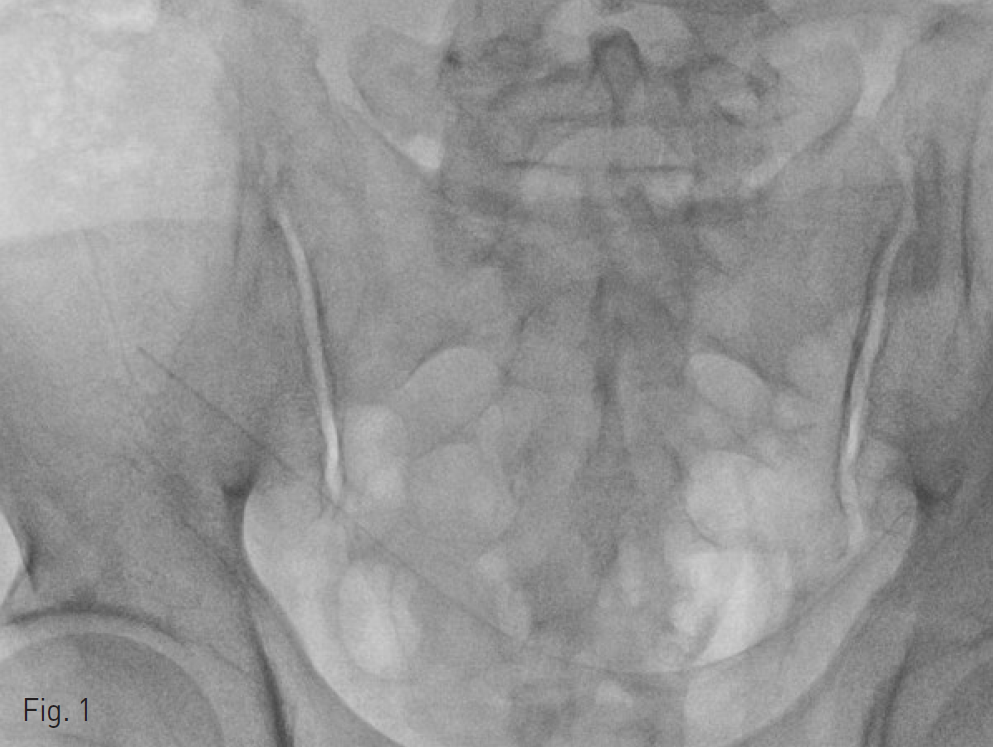

Fig. 1. Jackson Pratt drain tube tip in the pelvic cavity.